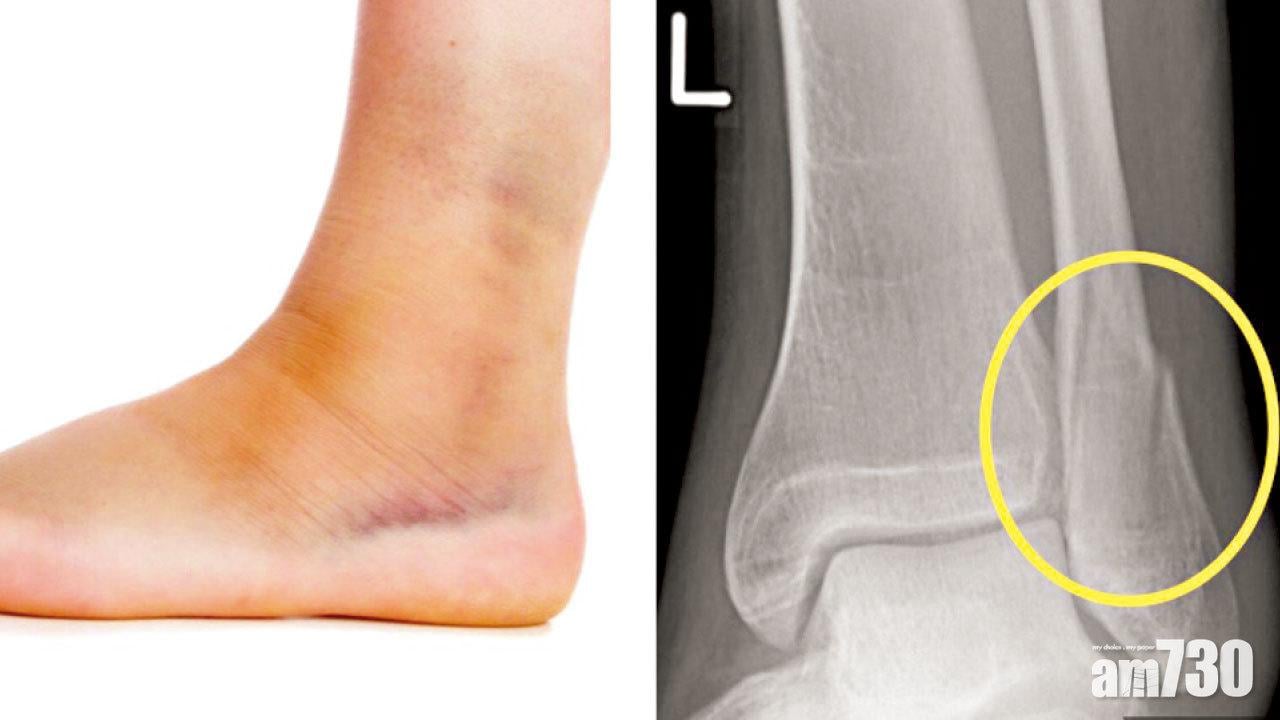

俗稱「腳眼」的踝關節,由脛骨遠端、腓骨遠端以及距骨組成,彼此以韌帶相連。一旦足踝扭傷,通常以內翻「拗柴」居多。此創傷姿勢,可導致外側的前距腓韌帶和跟腓韌帶撕裂,形成紅腫、瘀傷和痛楚。倘若足踝扭傷的力度過大,更會造成不同程度的踝關節創傷,包括腓骨遠端骨折、脛骨內踝骨折和相連韌帶撕裂等,足踝腫脹與疼痛會較純粹扭傷更為嚴重,傷者因痛更難以行走。

遇上同伴拗柴,又豈能捨他於荒野不顧,一個人拖篋回港?故此在環境許可下,應盡快施以RICE的急救方案:即是休息(Rest)、冰敷(Ice)、壓迫(Compression)和抬高(Elevation)。視乎受傷嚴重性,可考慮陪同他到當地醫療機構「投案」照X光。即使證實骨折,除非嚴重至皮膚破損、骨折外露的開放性骨折,或是踝關節出現骨折脫位,否則未必要留醫當地做手術。只需以石膏托穩定足踝並配上拐杖等助行器,便可盡快「引渡」回港接受進一步治療。

踝關節骨折是否須做手術,取決於骨折有沒有明顯移位,踝關節有沒有因骨折或韌帶撕裂而變得不穩定,和關節內有沒有軟骨碎片。如以上皆否,便適合保守治療,一般須打石膏約六星期左右,期間要靠助行器,讓患肢在非負重下行走。被不少病人形容為「坐監」的石膏治療,有別於石膏托或夾板,會完整地包圍踝關節,讓骨折置身在這「安全屋」內以防移位。但當骨折愈合,就要立即拆石膏,免得踝關節愈發僵硬。至於移位且不穩定的骨折,便必須做開放復位及內固定術,植入鋼片與螺絲。